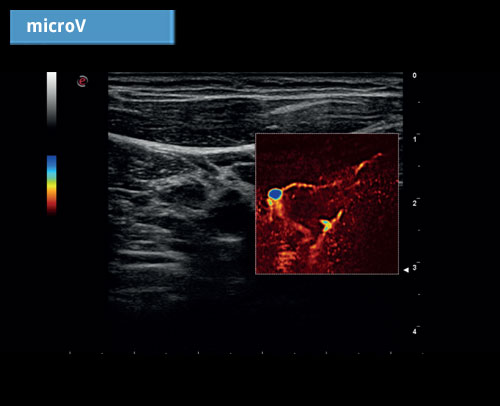

microV: Hemodynamické hodnocení s vysokou citlivostí a vysokým prostorovým rozlišením pro charakterizaci vaskularizace lézí ve všech klinických aplikacích, rychlé a neinvazivní.